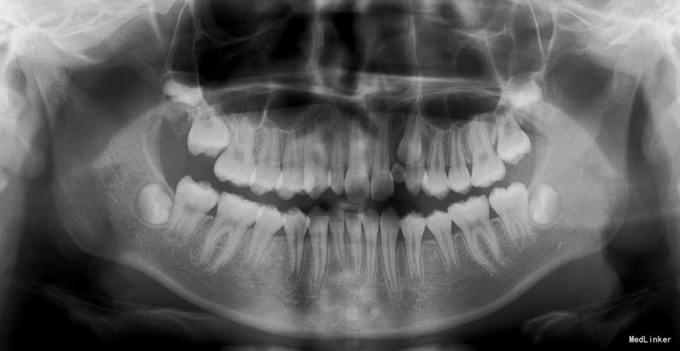

直面型,左上乳2仍存,口内未见恒2,下前牙口内只有3颗。上下牙齿轻度拥挤不齐。全景示下前牙先天缺失一颗,左上恒2垂直埋伏阻生。

诊断:先天缺牙;22牙埋伏阻生 治疗:排齐整平后,拔除乳侧切牙(先保留乳牙不拔的目的是为了保持骨量)然后开窗牵引恒2,先用弹力线逐渐加力,牙齿快移入牙弓的时候粘接拖槽,用12niti的辅弓辅助22牙排齐,同时主弓丝仍为1825ss维持弓形不变。